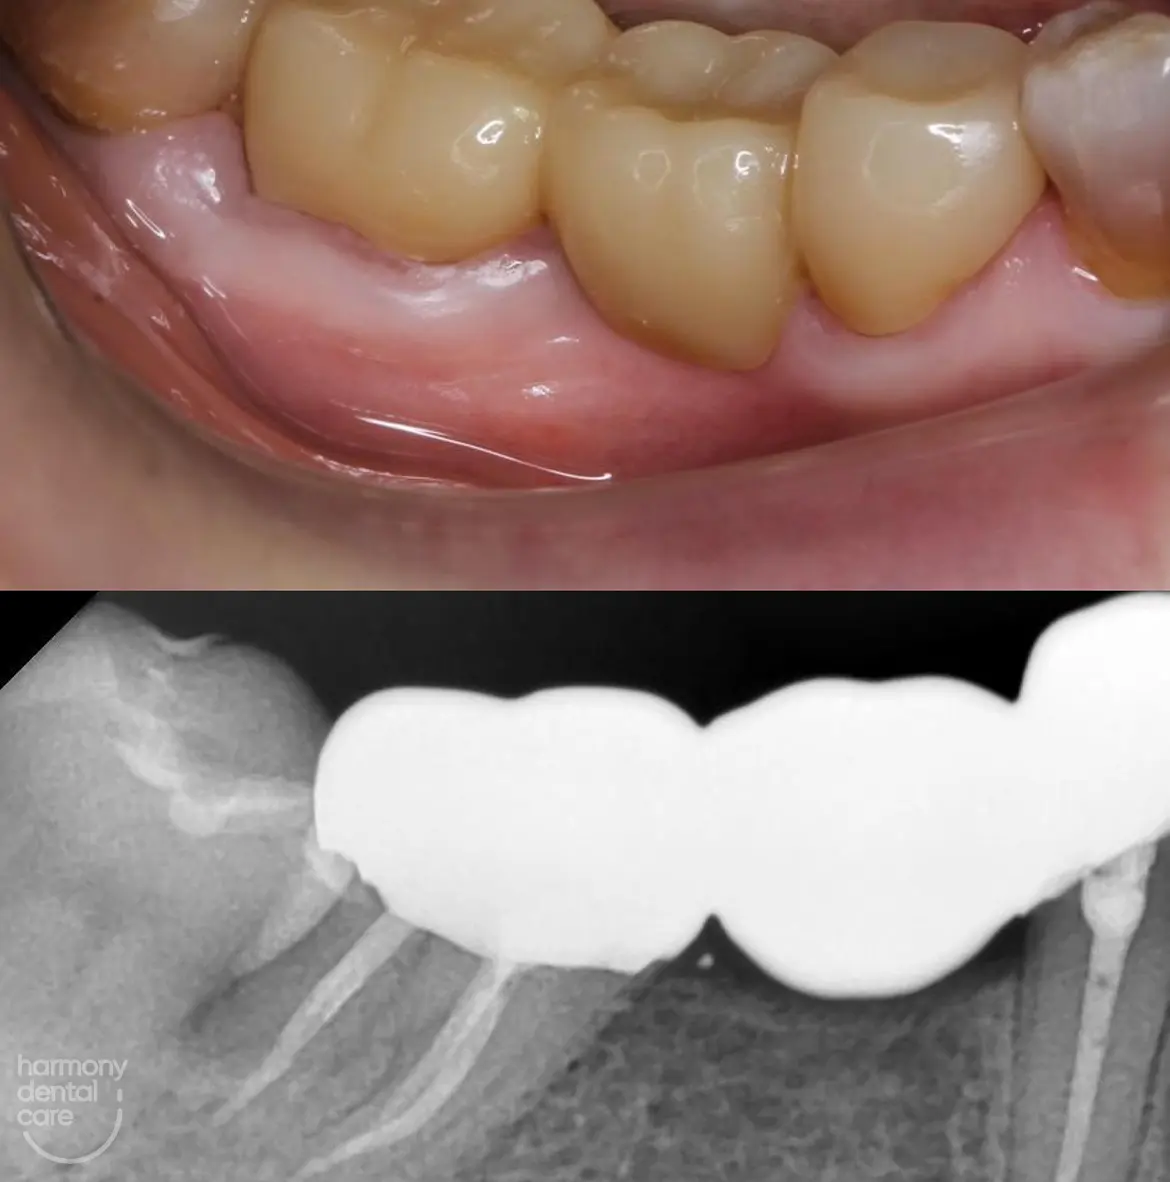

Karang gigi yang tidak pernah dibersihkan akan semakin menumpuk seiring waktu. Sisa makanan dan plak yang dibiarkan akan mengeras dan menjadi tempat berkembang biaknya bakteri. Hal ini dapat menyebabkan berbagai masalah seperti bau mulut, gusi berdarah, hingga peradangan serius yang dikenal sebagai periodontitis. Tidak hanya itu, penumpukan karang gigi juga dapat merusak enamel gigi dan menyebabkan gigi menjadi lebih sensitif terhadap makanan dingin atau panas.

Bagi Anda yang belum pernah membersihkan karang gigi dan khawatir karang gigi sudah terlalu menumpuk, jangan khawatir. Karang gigi yang menumpuk masih bisa dibersihkan dengan teknik pembersihan profesional seperti scaling. Dokter gigi akan menggunakan alat khusus untuk mengangkat karang gigi hingga ke sela-sela yang sulit dijangkau oleh sikat gigi biasa.

Semakin lama dibiarkan, karang gigi memang bisa menjadi lebih keras dan sulit dibersihkan dengan metode sederhana. Oleh karena itu, semakin cepat Anda mengambil tindakan, semakin baik pula hasilnya. Jangan ragu untuk berkonsultasi dengan dokter gigi agar Anda mendapatkan solusi yang tepat untuk masalah karang gigi Anda.

Jika Anda terus menunda membersihkan karang gigi, efeknya bisa sangat merugikan. Salah satu dampaknya adalah radang gusi atau gingivitis yang ditandai dengan gusi bengkak dan mudah berdarah. Jika dibiarkan, kondisi ini bisa berkembang menjadi penyakit gusi yang lebih serius yang dapat menyebabkan gigi goyang hingga tanggal.

Selain itu, penumpukan karang gigi yang berlebihan juga bisa menyebabkan penurunan jaringan pendukung gigi. Akibatnya, gigi bisa mengalami pergeseran posisi atau bahkan mengalami kerusakan permanen. Oleh karena itu, sangat penting untuk segera melakukan pembersihan secara rutin agar kesehatan gigi tetap terjaga.